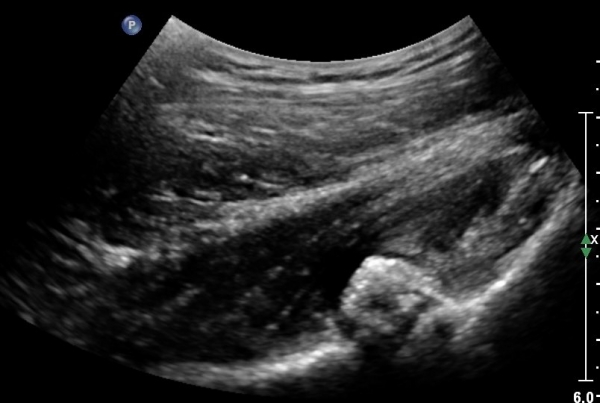

ÃÊÀ½ÆÄ°Ë»ç: °í°üÀý ¾ÕÂÊ Á¾´Ü¸é °Ë»ç¿¡¼­ °üÀý³¶ÀÌ µÎ²¨¿öÁö°í °æ¹ÌÇÑ °üÀý³» ºÎÁ¾À» º¸ÀÓ(»çÁø1, 2)